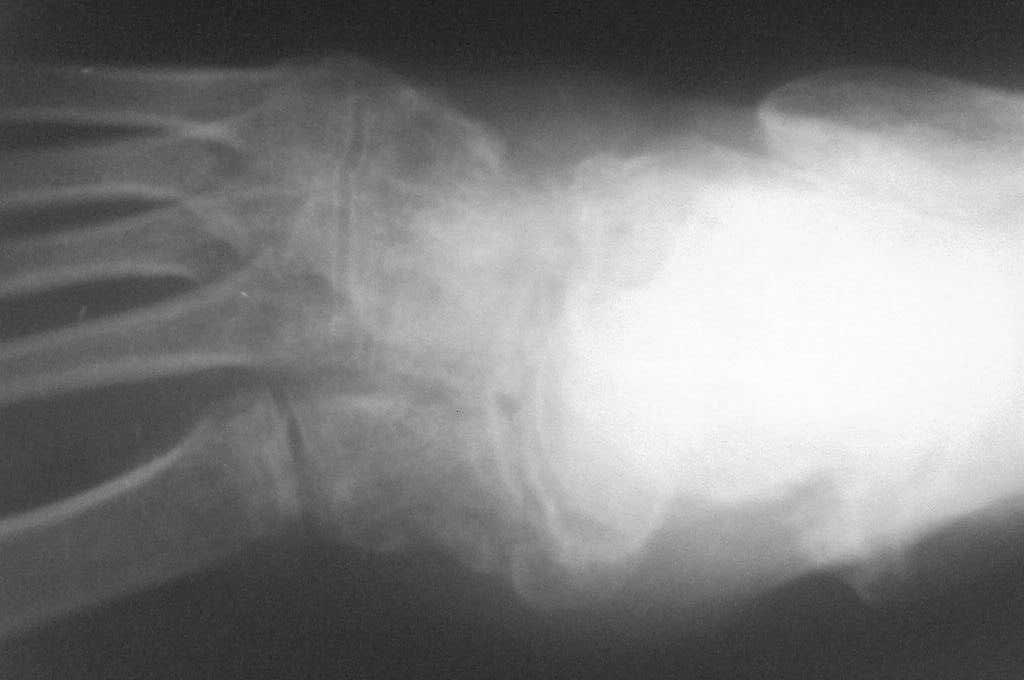

[Ortho] Застарелый вывых ладьевидной кости стопы

По  данному  случаю,  оказалось  3  месяца  назад  было  произведена Р-графия в  райбольнице,  но  больной предпочел  лечится  у  табиба. Присылаю  первичные  снимки.

Имя     : SP_A0176.jpg

Url     : http://weborto.net:8080/pipermail/ortho/attachments/20080406/e30b47f8/attachment-0002.jpg